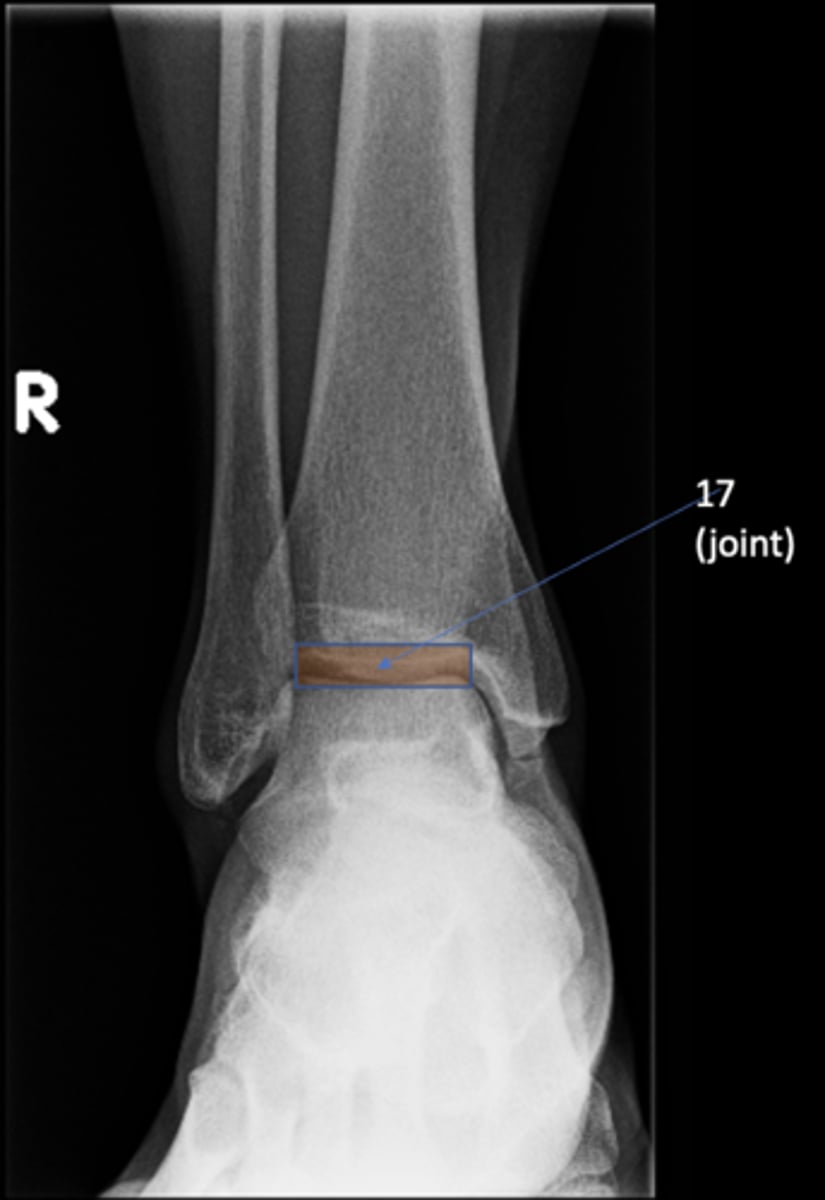

Right AP ankle

View?

<p>View?</p>

77

New cards

Lateral malleolus

ID 11

<p>ID 11</p>

78

Tibial plafond

ID 12

<p>ID 12</p>

79

Trochlea of talus

ID 13

<p>ID 13</p>

80

Distal tibiofibular joint

ID 14 (joint)

<p>ID 14 (joint)</p>

81

Tibiotalar joint

ID 17 (joint)

<p>ID 17 (joint)</p>